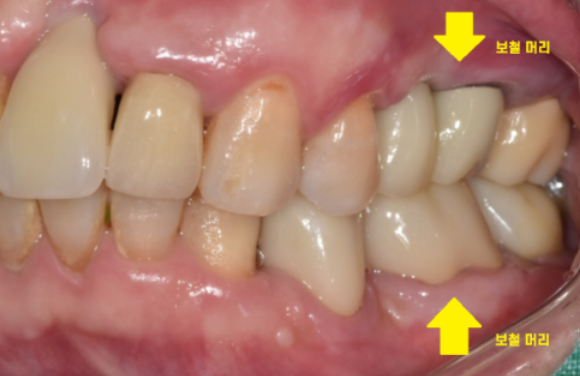

환자분이 생각하시는 머리는 이런 형태이실겁니다.

무언가를 씹을 수 있는..

뽄을 뜨는 것은 머리 부분에 해당하는

씹을 수 있는 무언가를 만들어주기 위해서입니다.

보철 제작을 완료하면

구강 내에 접착을 시행합니다.

이제 씹기도 하고 양치도 가능하며

내 치아처럼 사용이 가능합니다!!